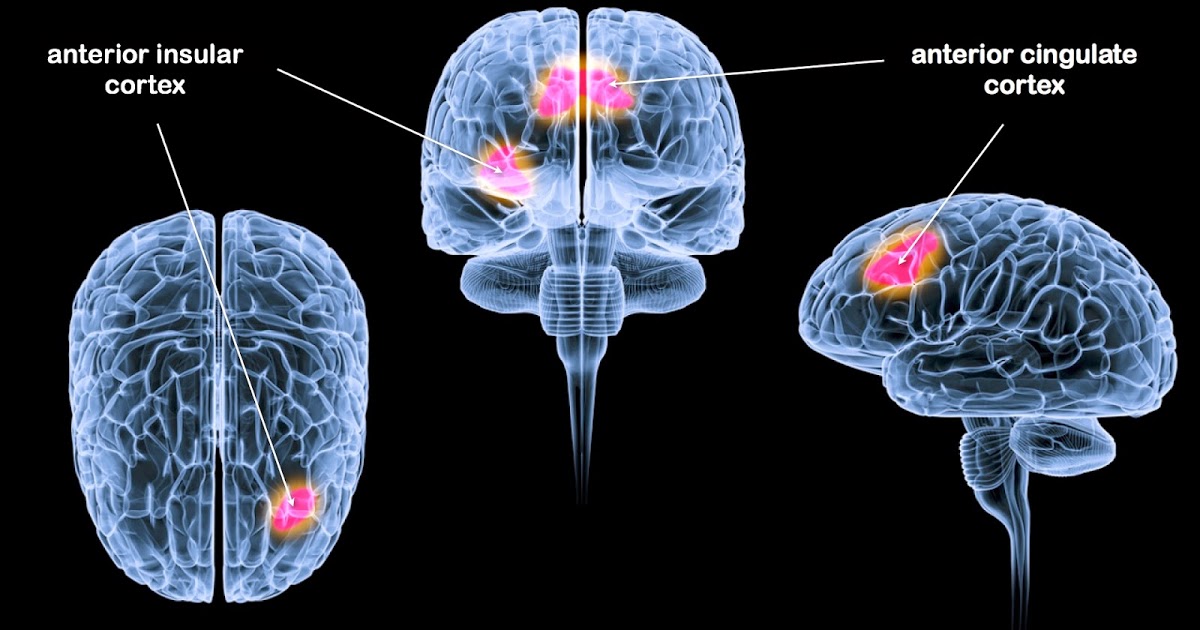

뇌의 활동 중에 DMN이라는 것이 있습니다.

우선 DMN이 무슨 뜻인지 부터 이야기 드리겠습니다. 우선 D는 Default라는 단어의 첫 글자입니다. 디폴트라는 단어는 부도, 불이행, 연체 뭐... 이런 부정적인 단어로 인식됩니다. M은 'Mode'라고 해서 형태, 방법, 상태를 뜻합니다. 그리고 마지막 N은 network라는 단어로 망, 통신망, 관계, 연계라는 뜻입니다.

초창기에는 이 DMN기능에 대해서 정말 부정적인 기능으로만 알고 있었지만 점점 뇌과학이 발전하면서 DMN의 긍정적인 기능을 발견하게 됩니다. 사실 이 DMN이라는 말은 2001년부터 사용된 단어입니다. 미국 마커스 레이클(Marcus Raichile) 교수가 처음 제안했던 개념입니다. 디폴트라는 것이 컴퓨터에서도 사용되는 표현입니다. 컴퓨터에서 디폴트라고 하면 그냥 리셋이 되어버려서 0으로 돌아가버리는 것을 말합니다. 이처럼 뇌가 그냥 멍~~~ 때리는 상태가 되는 것입니다. 그냥 많은 생각을 하다보면 너무 용량이 꽉 차서 뇌가 알아서 0으로 돌아가게 만드는 기능을 말합니다. 왜 이렇게 우리는 너무 정보를 많이 받다보면, 공부를 많이 하다보면, 스트레스를 많이 받다보면, 이렇게 디폴트 모드 네트워크(DMN = Default Mode Network) 상태로 자동적으로 돌아갈까요?

만약 DMN 기능이 손상되어서 너무 과도하게 작동을 하게되면 정신질환에 걸리게 됩니다. 특히 조현병이 오게 됩니다. 외부에서 들어오는 자극에 대해서 못 받아들이게 되는 것입니다. 외부 자극들을 못 받는다는 것은 자신의 내부 정보만 받아들이기 때문에 생기는 문제가 발생합니다. 이것이 바로 환청과 환시인 것입니다.

반대로 DMN 기능이 너무 활성화가 안 되면, 자페증이나 우울증이 오게 됩니다. 외부의 자극에만 민감하고 예민하게 반응을 하기 때문에 지나간 시간과 지금 이순간을 연결하지 못하게 됩니다. 앞으로 다가올 시간과 타인을 의미 있게 연결을 할 수가 없게 됩니다.

조금 쉽게 이야기 하면, DMN은 잡생각입니다.

잡생각이 너무 과도하게 일어나면 조현병이 일어나는 것이고, 너무 잡생각을 하지 못하면 자폐증에 걸리게 되는 것입니다. 적절한 잡생각은 인간에게 상당히 중요합니다. 잡생각을 할 때를 잘 생각해보면, 휴식을 취할 때입니다. 또 멍 때릴 때입니다. 먼 산을 볼 때이고 잠들기 직전과 잠에 빠져 꿈을 꿀 때 일어나는 것입니다. 이런 상태이기 때문에 DMN은 우리에게 상당히 중요한 기능인 것입니다. 그래서 기억과도 관련이 있습니다. DMN이 적절하게 활성화되어야 내가 학습한 내용을 조절하고 정리를 해주는 것입니다.